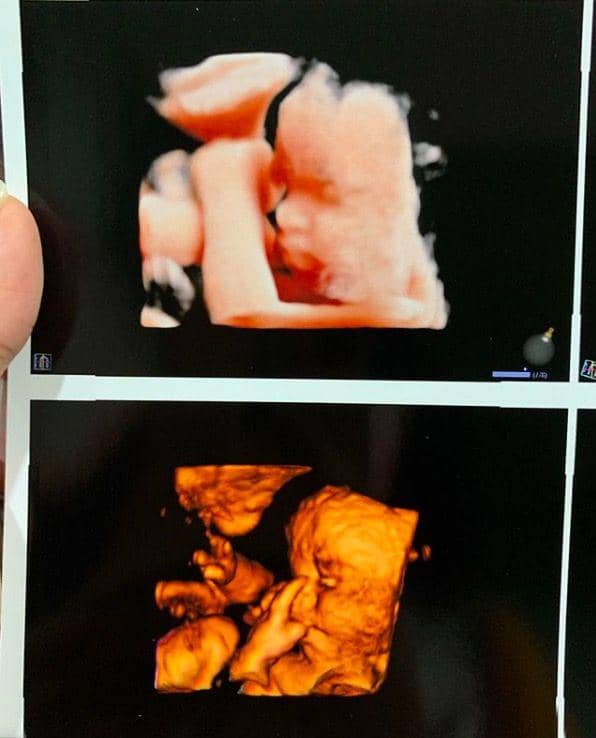

4. Vanessa pun sempat memamerkan hasil foto USG-nya saat usia kandungannya 28 minggu. Wajah Gala Sky sudah tampak jelas nih